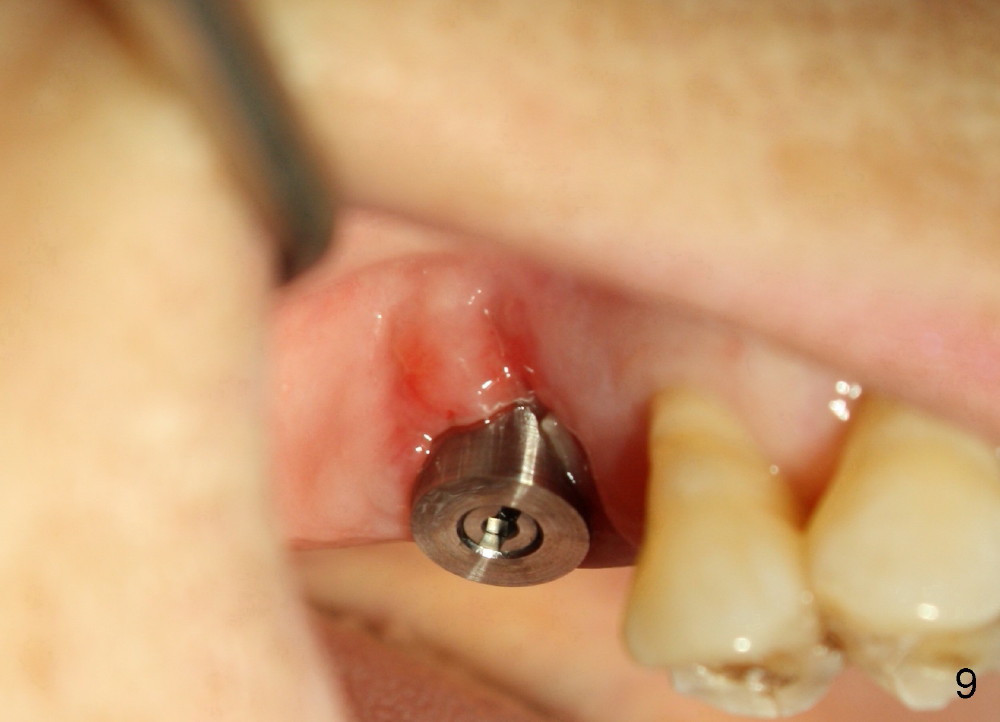

There is no nasal hemorrhage intra or postop. The implant is covered buccally by healing gingiva 7 days postop (Fig.9). It appears that the gingiva has strong regenerative potential. The buccal gingiva looks normal 3 months postop (Fig.10 healing cuff is placed over the implant). The implant appears to have osteointegrated (Fig.11).